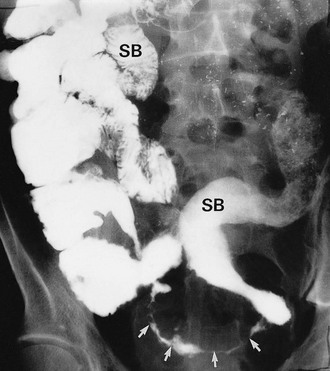

Colonoscopy enables a histological diagnosis to be obtained in colonic disease, and also allows biopsies of terminal ileum to be taken, which are often diagnostic. Barium ‘follow-through’ is the traditional method of examining small bowel but better images are sometimes obtained by controlled instillation of barium into the duodenum via a nasogastric tube. Typical radiological appearances of Crohn's disease include narrowing of the lumen due to mural oedema and fibrosis, nodularity and cobblestoning of the mucosal surface, deep fissured ulceration extending into the muscular wall, spiky ‘rose thorn’ ulcers and possibly evidence of fistula formation. Radiological changes in small and large bowel are shown in Figures 28.9 and 28.10. Note that large bowel abnormalities on barium enema may be difficult or impossible to distinguish from ulcerative colitis.

Appearances of Crohn's colitis are shown in Fig. 28.10.